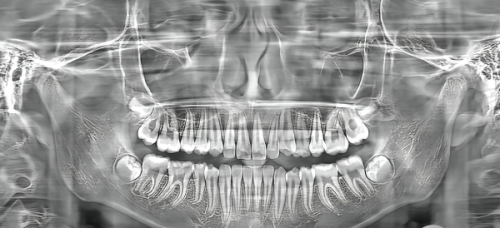

家人们,孩子的牙齿健康可是大事!特别多家长都关心小孩多大可以矫正牙齿,毕竟牙齿畸形不仅影响容貌,还可能影响孩子的口腔健康和心理健康。牙齿畸形的类型有特别多,像地包天、龅牙、牙列不齐等等,不同的畸形有不同的至佳矫正时机。了解这些知识,能让咱们在孩子牙齿矫正这件事上少走弯路,帮助孩子拥有一口整齐又健康的牙齿。接下来,咱们就一起详细了解一下儿童不同牙齿畸形对应的至佳矫正时机吧。

儿童牙齿畸形是比较常见的问题,不同的畸形表现对孩子的影响也不一样。下面就来看看几种常见的牙齿畸形。

地包天:也就是下排牙齿包住上排牙齿。从外观上看,孩子的下巴可能会比较突出,面型可能会呈现出“月牙脸”。这种畸形不仅影响美观,还会影响咀嚼功能,导致牙齿磨损不均匀。

龅牙:上排牙齿向前突出,嘴唇可能无法自然闭合,笑起来时牙齿会显得特别突出。龅牙会影响孩子的面部美观,还可能导致孩子产生自卑心理。

牙列不齐:牙齿排列不整齐,有的牙齿可能会歪歪扭扭,或者出现牙齿拥挤的情况。牙列不齐不仅影响美观,还容易藏污纳垢,增加龋齿和牙周炎的发病几率。